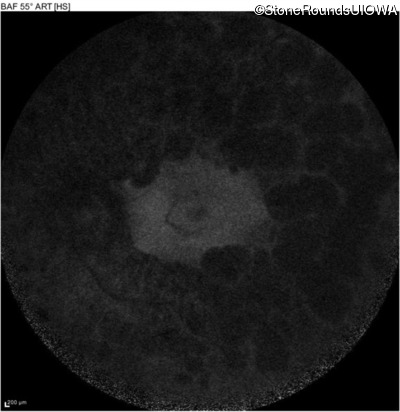

Infrared Fundus Photograph - Left - 20/50

Exemplar